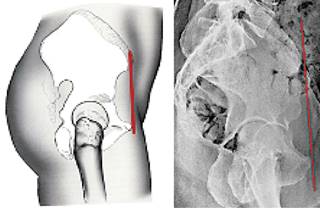

Plano anterior de la pelvis o plano de Lewinnek.30 Es la línea que une las espinas ilíacas anterosuperiores y la sínfisis del pubis. Este parámetro se ha convertido en la referencia dorada por los cirujanos de cadera para medir la magnitud de la movilidad pélvica (Figura 11).

El plano anterior de la pelvis (PAP) se define como una línea que une al eje biespinal superior (espinas ilíacas anterosuperiores) con la sínfisis del pubis y forma un ángulo con la línea vertical (plano coronal). Cuando el ángulo se abre hacia el frente, se dice que es un PAP positivo; cuando se abre hacia atrás se dice que es un PAP negativo.31 Los reportes de mediciones son muy diversas y dependen en qué posición o postura fueron hechas: de pie o en decúbito dorsal, en pacientes con trastornos vertebrales o posturales, etcétera. DiGioia27 reporta un promedio de -2o y rango entre -22o a +27o, medidos en posición de pie; Philippot32 obtiene -12o medidos en posición de pie, mientras que Maratt33 reporta una media de 0.6o ± 7.3o y un rango de +19.0o a -17.9o medidos en posición supina dorsal. En el estudio hecho por Kanawade,34 las pelvis normales (sin rigidez ni hiperelasticidad) rotan posteriormente de 20o a 35o al pasar de una posición de pie a sentada y las pelvis rígidas tienen en promedio 4o menos rotación que las pelvis normales y 13o menos que las pelvis hipermóviles. Se reitera que los reportes de mediciones del plano anterior de la pelvis son muy variables, ya que dependen de en qué posición o postura fueron hechos. Se debe tener mucho cuidado con la interpretación de esta medición.